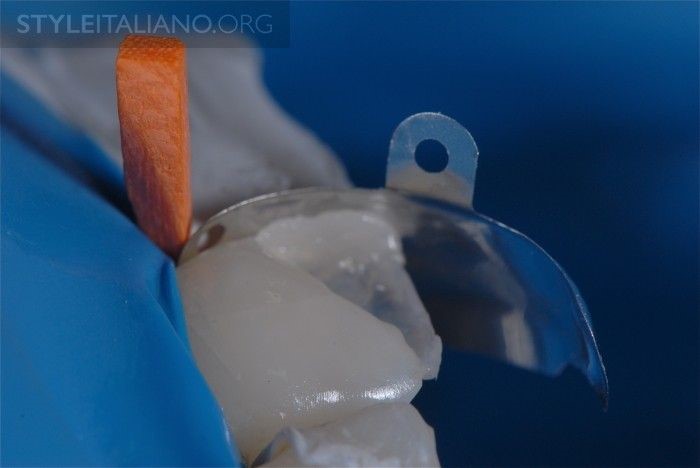

Hình 17. Sử dụng đai trám kim loại cho răng sau khi dựng lại mặt bên gần của răng bằng composite màu men (trường hợp này tác giả dùng màu A3 Enamel, 3M ESPE). Nên đặt chêm gỗ để giữ ổn định vị trí của đai trám và tách biệt hai răng giúp tái tạo điểm tiếp xúc bên chặt hơn.